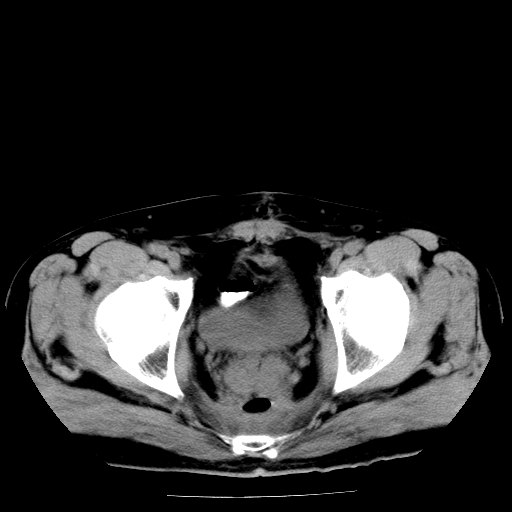

男,66岁,直肠癌术后一个月,化疗前ct检查。

前列腺大,直肠壁厚,造瘘术后

结肠造瘘术后。

直肠癌周围浸润。

前列腺肥大。